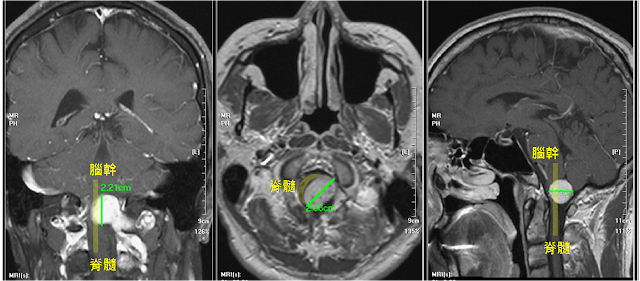

腫瘤位於頸椎第一節和枕骨大孔之間

把脊髓壓得扁扁的

正常的脊髓從橢圓形被壓成新月形

腫瘤皆影響到椎動脈

椎動脈是供應腦幹血液的動脈